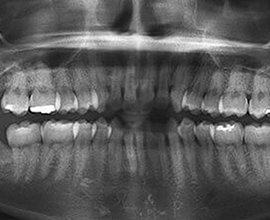

• 術後 画像

術後

奥歯まで きちんとブラシが届くようになり、隣の歯の虫歯を回避することができました。手術自体は1時間程度、左右に分けて抜歯を行いました。